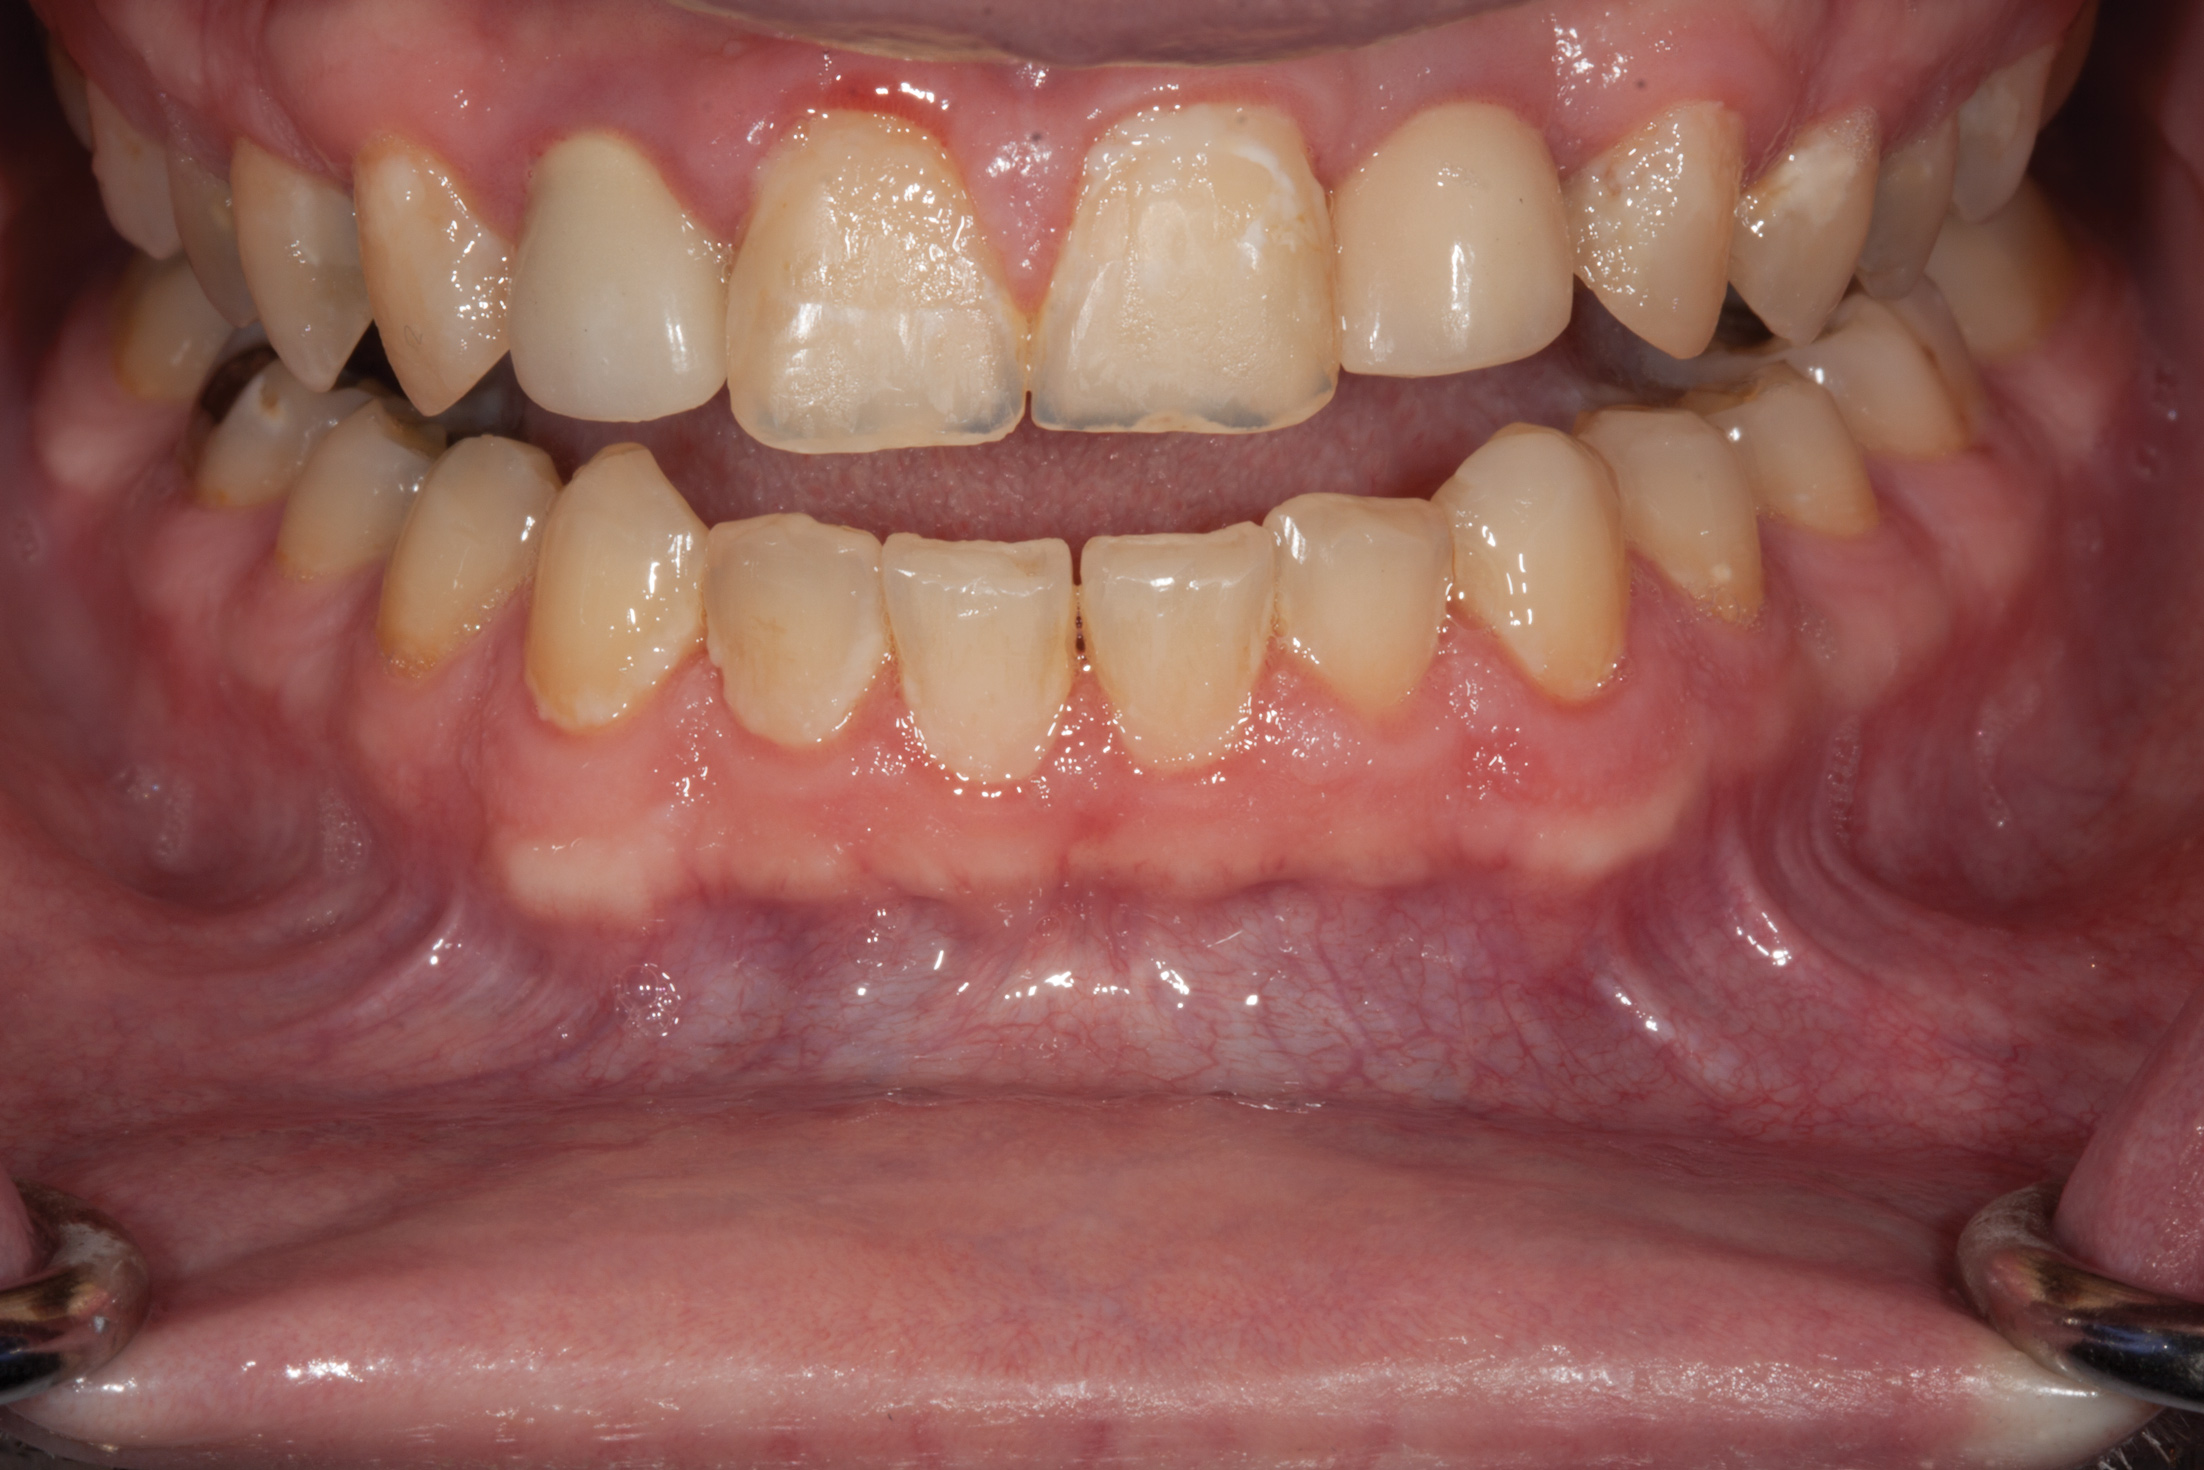

Fig 2. Facial view of worn dentition from erosion.

Figure 2

Fig 12. Prosthetic phase completion. Facial view. Note the more ideal horizontal overlap of anterior teeth and robust periodontal phenotype. Horizontal positioning of anterior teeth was enabled as a result of bone augmentation.

Figure 12